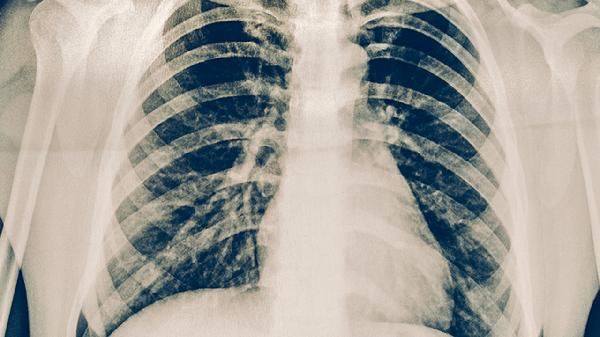

治療期間每1-2個月需進行痰涂片檢查、胸部X線或CT復查,評估病灶吸收情況和痰菌轉陰狀態(tài)。痰菌持續(xù)陽性者需調(diào)整用藥方案,治療6個月后未轉陰可能需延長療程至9-12個月。治愈標準需滿足臨床癥狀消失、影像學顯示病灶穩(wěn)定、痰菌連續(xù)3次陰性。糖尿病患者、HIV感染者等特殊人群需加強血糖控制和免疫狀態(tài)監(jiān)測。